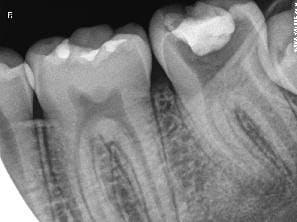

Je vous demande conseil pour la dent 37 que vous pouvez voir ci joint.

Le patient se présente avec une douleur non rémanente, non pulsatile. Je sonde et trouve un point de carie ressemblant à un point de carie arretée, mais je m'enfonce allègrement avec la sonde, je prend la radio (voir "sans titre"), je vois cette carie "surprise" :)

Radio faite : voir "Sans titre 2"

Je ne trouve rien de changer...pour la racine mésiale en tout cas, mais apres avoir tenté de prendre l'apex distal 4 fois et quil est failli me vomir dessus a chaque reprise, j'ai abandonné...